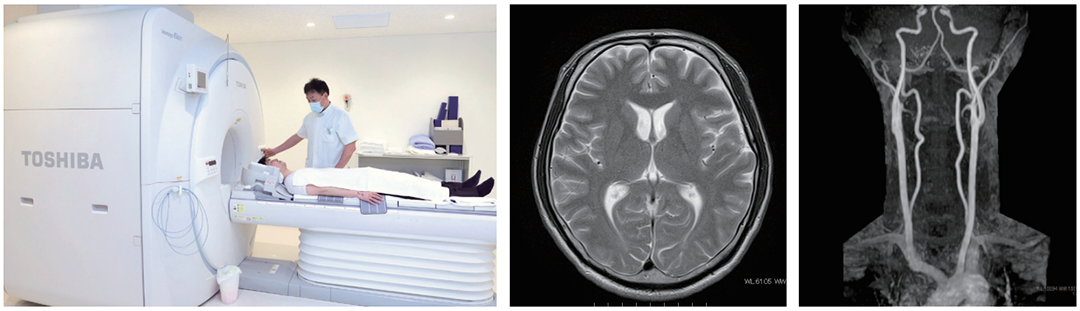

脳ドックとは、発症してしまうと後遺症や生死に関わるような脳の疾患を早期に発見し、予防や進行の防止につなげるための検査です。

主な検査内容は以下の通りです。

- 頭部MRI検査

- 頭部MRA検査

- 頸部MRA検査

※MRA:脳に血液を送る血管を撮影する検査です。